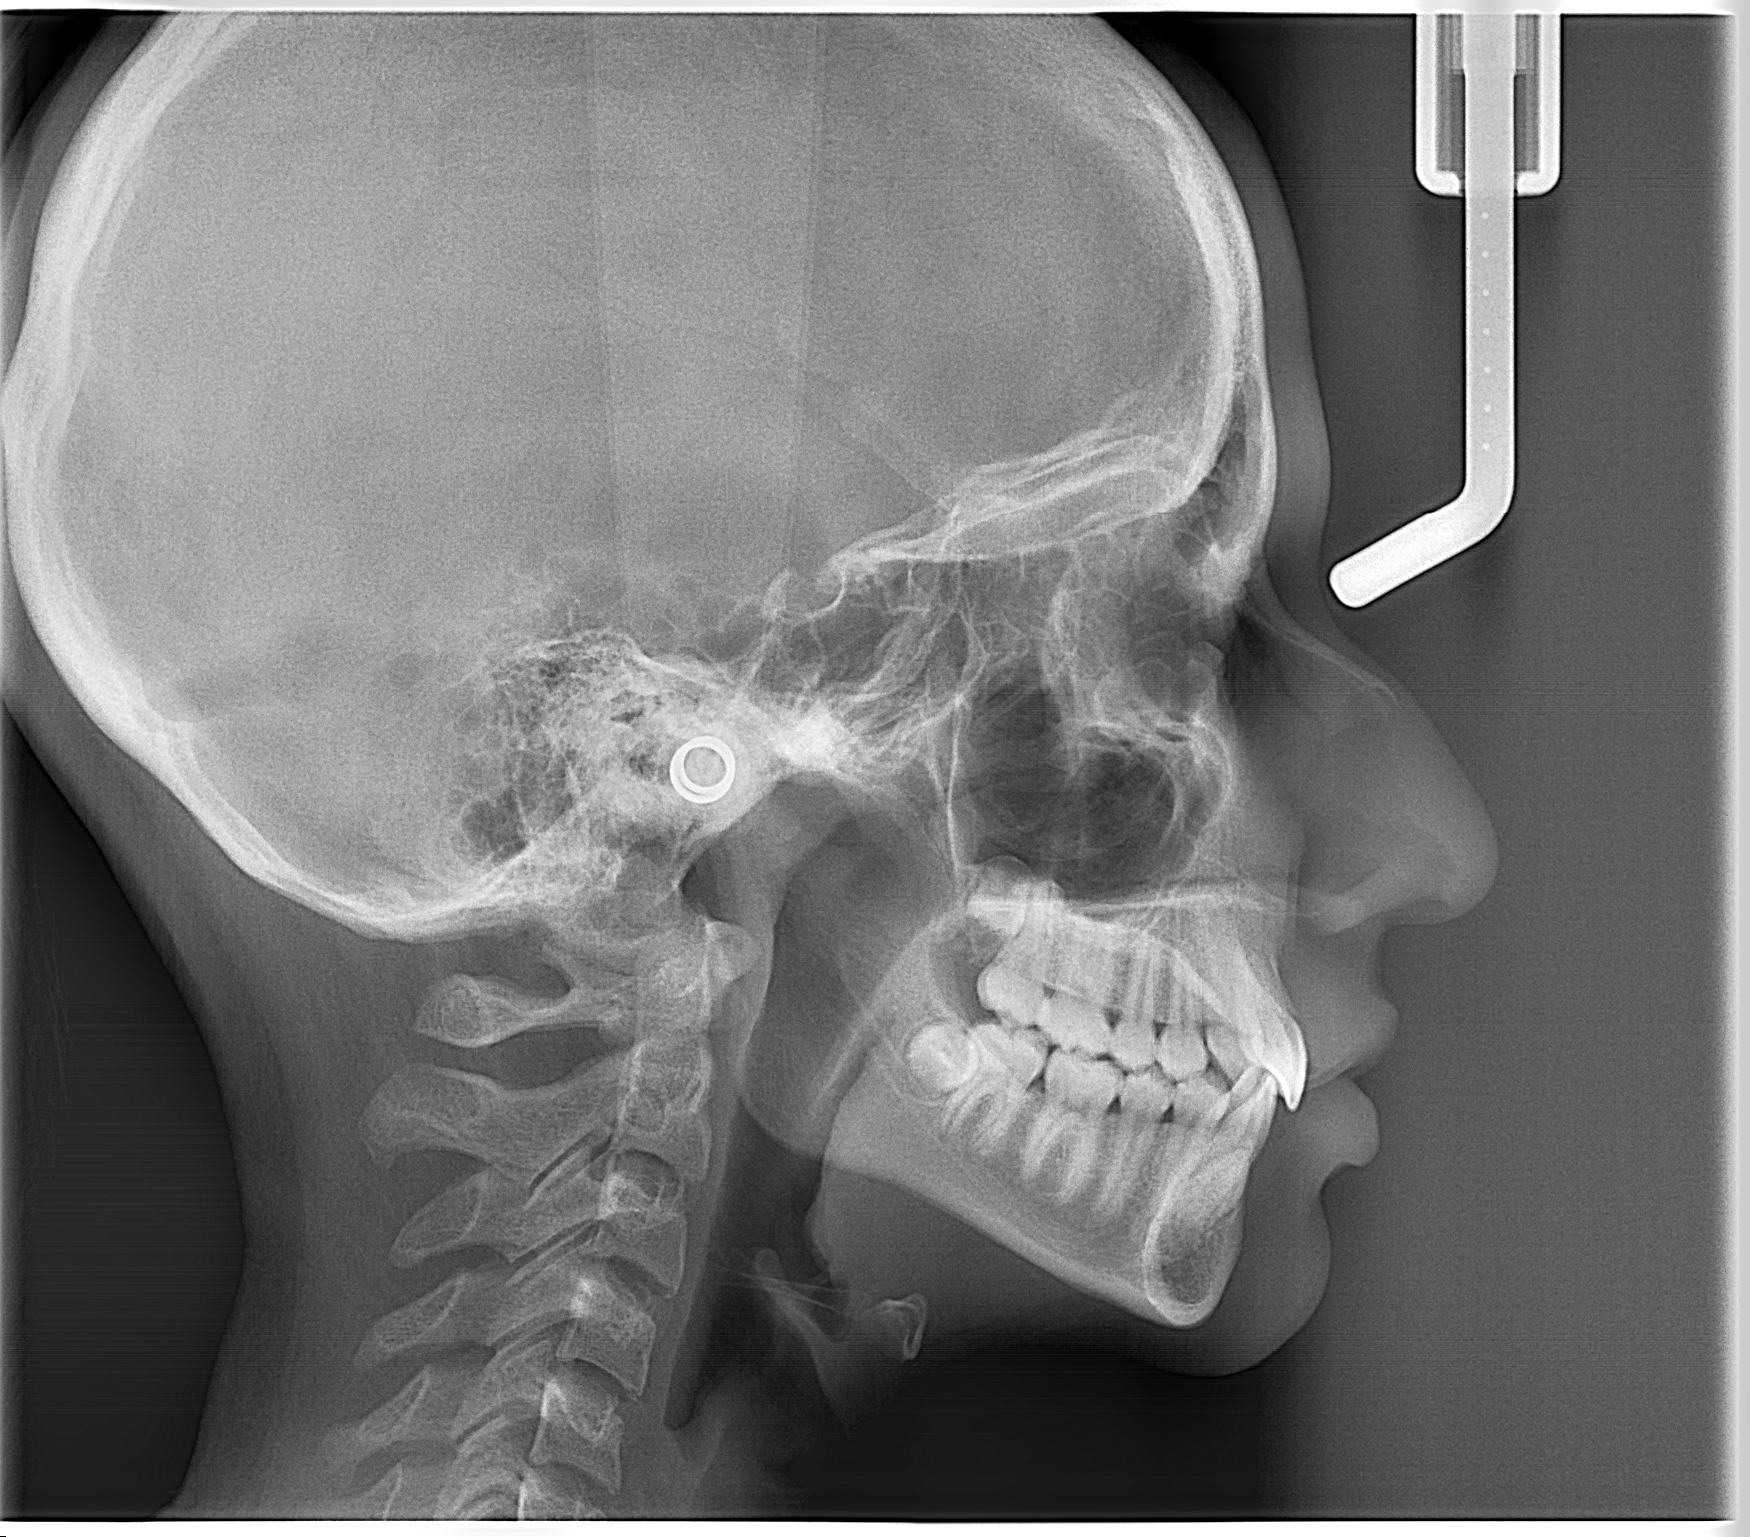

- Radiografía cefálica lateral: Radiografía extraoral que permite evaluar permeabilidad de vía área, ver el tamaño y posición de los maxilares, permite identificar la relación intermaxilar, entre otros.

Esta radiografía ayuda a evaluar la permeabilidad de vías aéreas, el tamaño y posición de los maxilares, y la relación intermaxilar.